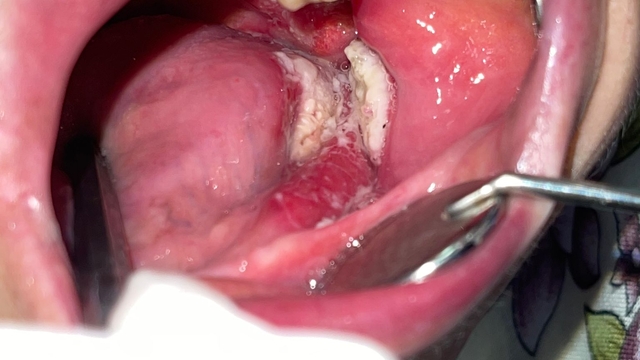

Ağız kanserinde erken tanı gerçekleşirse hastaların ölümle sonuçlanmasının önüne geçilebileceğini ifade eden Prof. Dr. Gündüz, “Biz kurum olarak Karadeniz'in en büyük üniversitesiyiz ve de fakülte olarak da Karadeniz'de büyük bir hizmet vermekteyiz. Ortalama yaklaşık günde 500 hasta, aylıkta 10 bine yakın hasta bakıyoruz. Biz yapmış olduğumuz seminerlerde hem öğrencilerimizi hem asistanlarımızı hem de halkımızı bu konuda bilgilendirmeye çalışıyoruz. Erken tanı eğer gerçekleşirse bu hastalıkların ölümle sonuçlanmasının nispeten önüne geçmiş oluyoruz. Çünkü erken tanı biliyorsunuz her kanser vakasında çok önemli bir yer tutmakta. Herhangi birisi ağzında eğer 2 haftanın üzerine geçmeyen bir yara varsa mutlaka en yakın diş hekimine başvurması gerekmekte. Sebepsiz yere dişlerin sallanması, uyuşukluk olması, yüzde sebepsiz ağrıların, çene bölgesinde sebepsiz ağrıların oluşması kanserlerin başlangıç bulguları arasındadır. Zaten kanserlerin en fazla oluştuğu yerler ağız içerisinde dilin özellikle arka kenarlarıdır. Bunlar ne yazık ki başlangıçları da ağrısız olduğu için bir kısmının gözden kaçabilmekte. O yüzden insanlarımızdan, halkımızdan bu konuda dikkat etmeleri, eğer böyle bir lezyonla muhatap olurlarsa mesela bir yakınından ağız içerisindeki görüntüsünü çekmesini talep etmeli. 2 hafta sonra da aynı şekilde bu görüntü duruyorsa veya daha da büyümüşse en yakın merkeze gitmesini önermekteyiz” ifadelerini kullandı.

Ağız kanserinin bulaşıcı olmadığını belirten Gündüz, “Bir kere insanlar şöyle de düşünüyor, diş kanseri var mı? Şimdi diş kanseri diye bir şey yok. Oral kanserler dediğimiz şey, dudaklar değil, diş eti, yumuşak damak, sert damak dediğimiz bölgeyi kapsar. Oral kanserlerin, tüberküloz gibi, bir hepatit gibi bulaşma şansı bulunmamaktadır. Yani bireyin kendisinde olur, kaybolur veya hastayı ne yazık ki ölüme götürür. Yani bulaşmaz” diye konuştu.